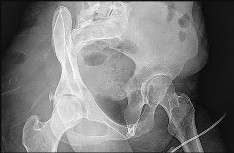

A 13-year-old obese male presents with acute-on-chronic hip and knee pain and an inability to bear weight on the affected limb. Radiographs confirm an unstable slipped capital femoral epiphysis (SCFE). He is taken to the operating room for urgent in-situ pinning. What is the most significant complication associated with attempting a forceful, intentional closed reduction of this deformity prior to hardware placement?

Correct Answer: Femoral head osteonecrosis (avascular necrosis)

Explanation:

An unstable SCFE (defined as the inability to bear weight even with crutches) already carries a high risk of osteonecrosis. Attempting a forceful closed reduction further disrupts the fragile retinacular vascular supply to the femoral epiphysis, significantly increasing the risk of iatrogenic avascular necrosis. Gentle reduction by positioning may occur naturally, but intentional forceful reduction is contraindicated.